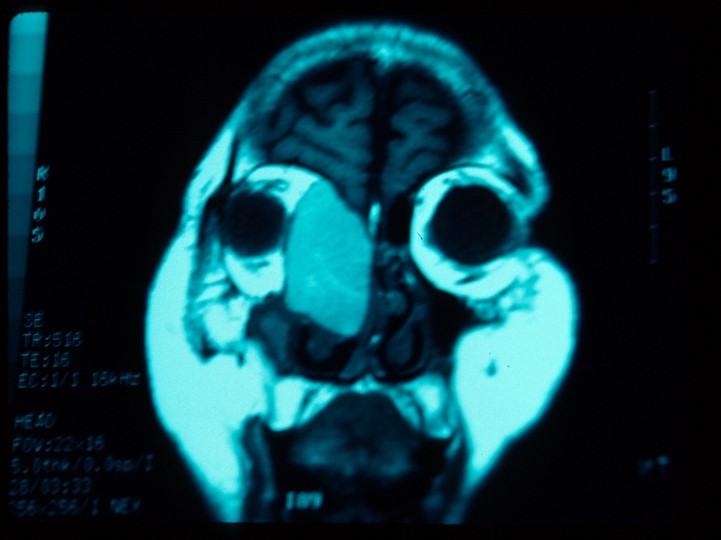

Diagnosis is primarily made via imaging. Both computed tomography (CT) and magnetic resonance imaging (MRI) can be utilized to aid in diagnosis. The appearance of mucoceles on imaging can be variable depending on whether the mucocele contents are inspissated or hydrated.[15] . CT is helpful in assessing sinus pathology and extent of bone erosion. A mucocele is most commonly isodense with the brain. Contrast enhancement of the lesion on CT suggests infection. MRI is helpful in assessing the extent of the lesion and in differentiating the lesion from other soft tissue tumors. Most commonly, the lesion appears with low intensity signal on T1-weighted sequence with possible peripheral enhancement and with high intensity on T2-weighted sequence.[2] Lesions with inspissated contents have low intensity signal in T1-weighted and T2-weighted sequences while hydrated or proteinaceous contents will show high intensity signal in T1- and T2-weighted sequences.[15]